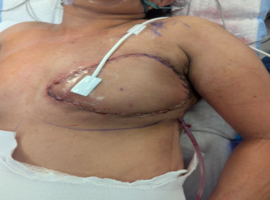

Carcinoma en Cuirasse Following Bilateral Mastectomy for Breast Cancer: A Case Report

Corneille ST*, Evrard S, Stephane K, et al. (Côte d’Ivoire)